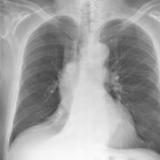

RLL Collapse 2 PA only

Date: 02/28/2004

Views: 3186